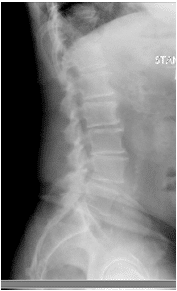

X-rays and MRI of the Lumbar spine showed L4-5 degenerative spondylolisthesis

and severe spinal stenosis.